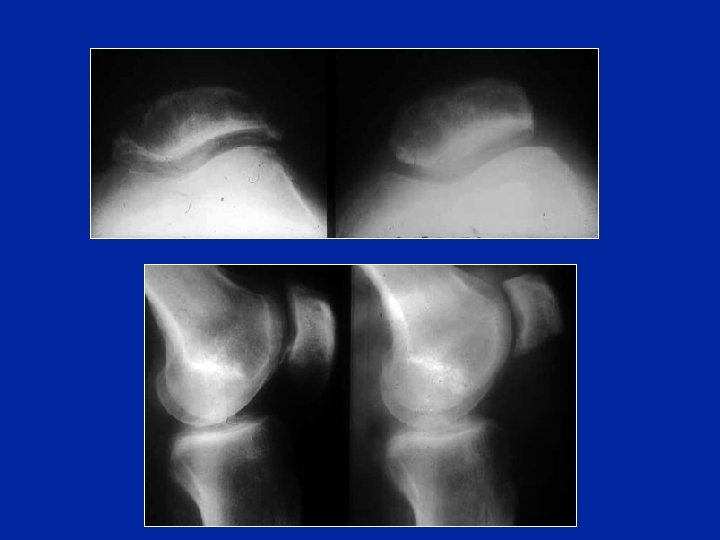

Diagnosi differenziale Patella bipartita o tripartita Anomalie congenite spesso bilaterali (possono divenire simtomatiche dopo un trauma)

Patella bipartita A volte dolorosa (necessario a volte la regolarizzazione chirurgica)